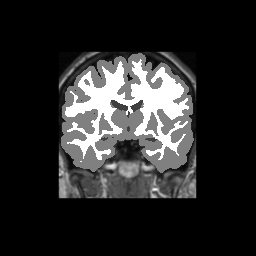

Accuracy is reported as Dice overlaps between a tool's segmentation and the Internet Brain Segmentation Repository (IBSR) manual segmentation for each of the 18 IBSR subjects. The inter-tool comparison (on the left below) shows the median Dice coefficient for each tissue class. The overlaps for FSL (from which the median values are drawn) are shown in the plot on the right.

Overlap coefficients for each tissue class are shown here for each IBSR subject. Select a subject below to see the FSL results compared to other tools.